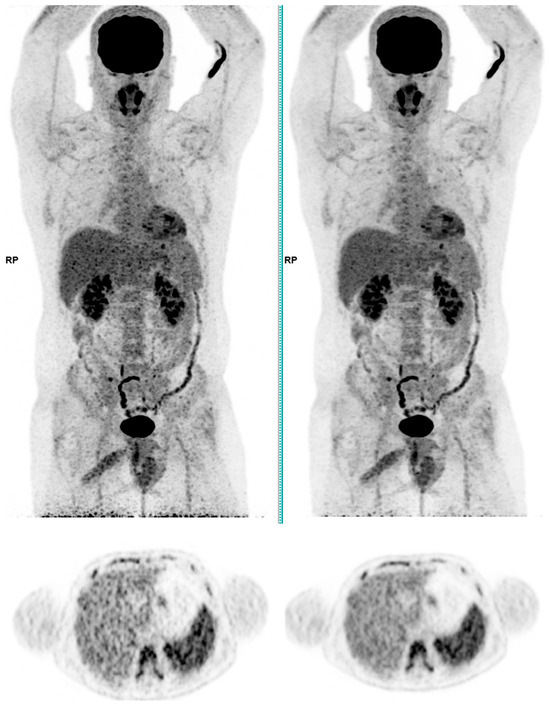

Across the three radiotracers, the AI-denoised images demonstrated a significantly improved performance in the visual analysis compared to conventional PET images. AI-denoised images were rated as interpretable (scores of 3–5) in all cases, compared to 65% for conventional images. Furthermore, an excellent image quality (score of 5) was achieved in 85% of all AI-denoised images, a significant improvement compared to the 50% in standard acquisitions. SubtlePET™ processing resulted in consistently lower noise levels, particularly for 18F-FDG scans, where 85% of images scored 4 or 5 for noise reduction compared to 60% in conventional scans. Lesion detectability was maintained or enhanced across all radiotracers, ensuring no compromise in the diagnostic accuracy. For 18F-FDOPA, a tracer with inherently lower signal-to-noise ratios, the AI algorithm improved the detection confidence by 25% compared to standard protocols. The visual comparison is illustrated through different MIP images and transaxial images (Figure 1, Figure 2, Figure 3 and Figure 4)

Figure 2. Total body 18F-FDG PET CT, MIP and transaxial images (left: without AI denoising; right: with AI denoising).